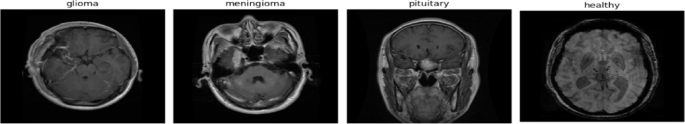

A swarm intelligence-driven hybrid framework for brain tumor classification with enhanced deep features

Scientific Reports - A swarm intelligence-driven hybrid framework for brain tumor classification with enhanced deep features